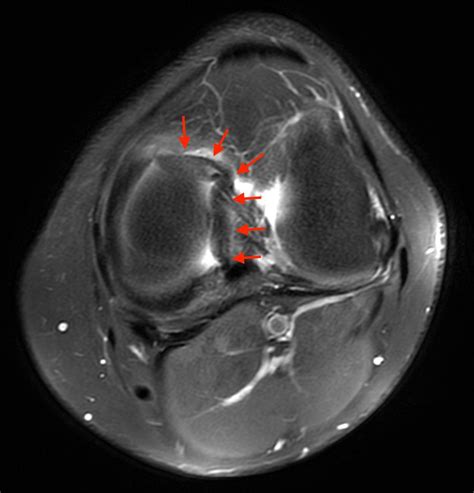

A bucket handle injury is a specific type of meniscal tear where the torn piece of the meniscus flips into the joint space, resembling the handle of a bucket. This type of tear is often more severe and can cause the knee to lock or give way. The meniscus is a C-shaped piece of cartilage that cushions the knee joint and helps distribute weight evenly. When it tears, it can lead to a range of symptoms that affect mobility and quality of life.

• Imaging Tests: X-rays, MRI, or CT scans may be ordered to visualize the meniscus and confirm the diagnosis. MRI is particularly useful for detecting meniscal tears and assessing the extent of the damage.